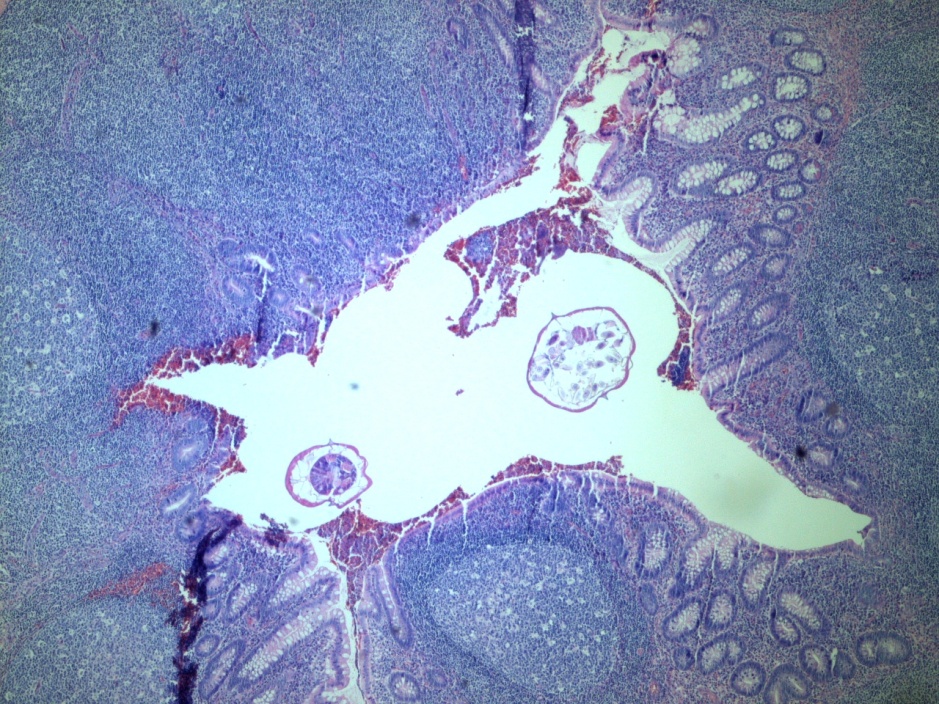

The bronchoscopy revealed a bloody fluid admixed with clots which was clinically consistent with diffuse alveolar hemorrhage. The roundworms depicted above were identified in both the BAL and stool O&P exam. Based on the presence of the short buccal cavity and the prominent genital primordium and the absence of eggs, the identification of Strongyloides stercoralis was made. Given the large amount of larvae present in both the lungs and gastrointestinal tract, the patient was diagnosed with a strongyloidiasis hyperinfection.

In the laboratory, the diagnosis of S. stercoralis is most often made by an ova and parasite exam of the stool, duodenal fluid, sputum or BAL specimens (Image 1). Most commonly the rhabditiform larvae are present and are identified by the presence of a short buccal cavity and prominent genital primordium (Image 2). These two features are helpful in distinguishing S. stercoralis from hookworms (Ancylostoma spp. and Necator americanus) which have a longer buccal cavity and indistinct genital primordium. The eggs of these two nematodes are also very similar, although typically S. stercoralis eggs hatch before they are passed in stool specimens. S. stercoralis can also be visualized on H&E histology sections in the crypts of intestinal biopsies where the adult female measures up to 2.2 mm in length. Finally, serologic testing can be helpful when there is a high suspicion of disease in the face of multiple negative stool exams, but cannot distinguish between a current or past infection. Most patients do not remember a specific exposure and prevention includes wearing gloves and shoes when handling or walking on soil that may contain contaminated fecal material. Treatment options for an acute or chronic S. stercoralis include a short course of ivermectin or albendazole. In the case of disseminated infection, ivermectin should be given until stool and sputum exams are negative for 2 weeks. In the case of our patient, she was started on ivermectin, but succumbed to the disease due to extensive pulmonary hemorrhage.